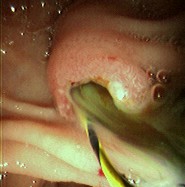

Foto endoscópica do mesmo paciente após remoção de grande cálculo do ducto colédoco; drenagem abundante de pus através da ampola

Do acervo de Douglas G. Adler; usado com permissão